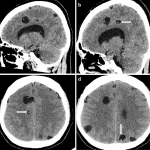

Nhiễm ấu trùng sán dây lợn hệ thần kinh trung ương (Neurocysticercosis) là bệnh ký sinh trùng phổ biến nhất của hệ thần kinh và là nguyên nhân chính của bệnh động kinh ở các nước đang phát triển. Biểu hiện lâm sàng phụ thuộc vào: số lượng, vị trí, giai đoạn phát triển ấu trùng ở não. Các nang sán có thể ở não, tủy sống, mắt, cơ và mô dưới da…